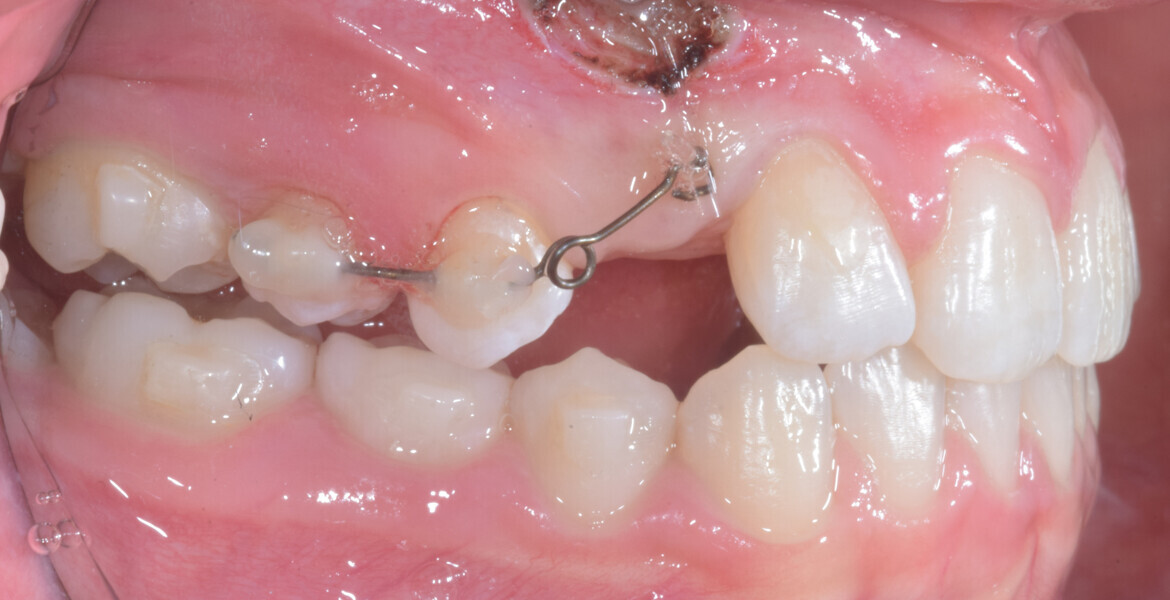

At the end of the first stage of aligner treatment (Figs. 20–24), the auxiliary phase began with the bonding of two MTAs on the maxillary right premolars. A 0.016-in Australian archwire, shaped into a cantilever configuration, was then inserted into the MTAs, and a cutout was created on the final aligner. To prevent rotation, the archwire was cinched distal to tooth #15 and the cinch covered with composite.

At the same time, the impacted canine was exposed by laser, a button was bonded on to it and the cantilever was connected to the button using an elastomeric thread. The final aligner was used for space maintenance while the cantilever was reactivated until the canine had erupted (Figs. 25–27). After complete eruption, further MTAs were bonded on the canine and on the lateral incisor, and a 0.014 in. NiTi archwire was used to finalise the eruption (Figs. 28–30). Only at the end of the forced eruption phase did the further aligner stage take place, aimed at achieving an ideal Class I relationship on the right by maxillary right mesialisation using Class III elastics and 27 maxillary aligners and 13 mandibular aligners (Figs. 31–33).